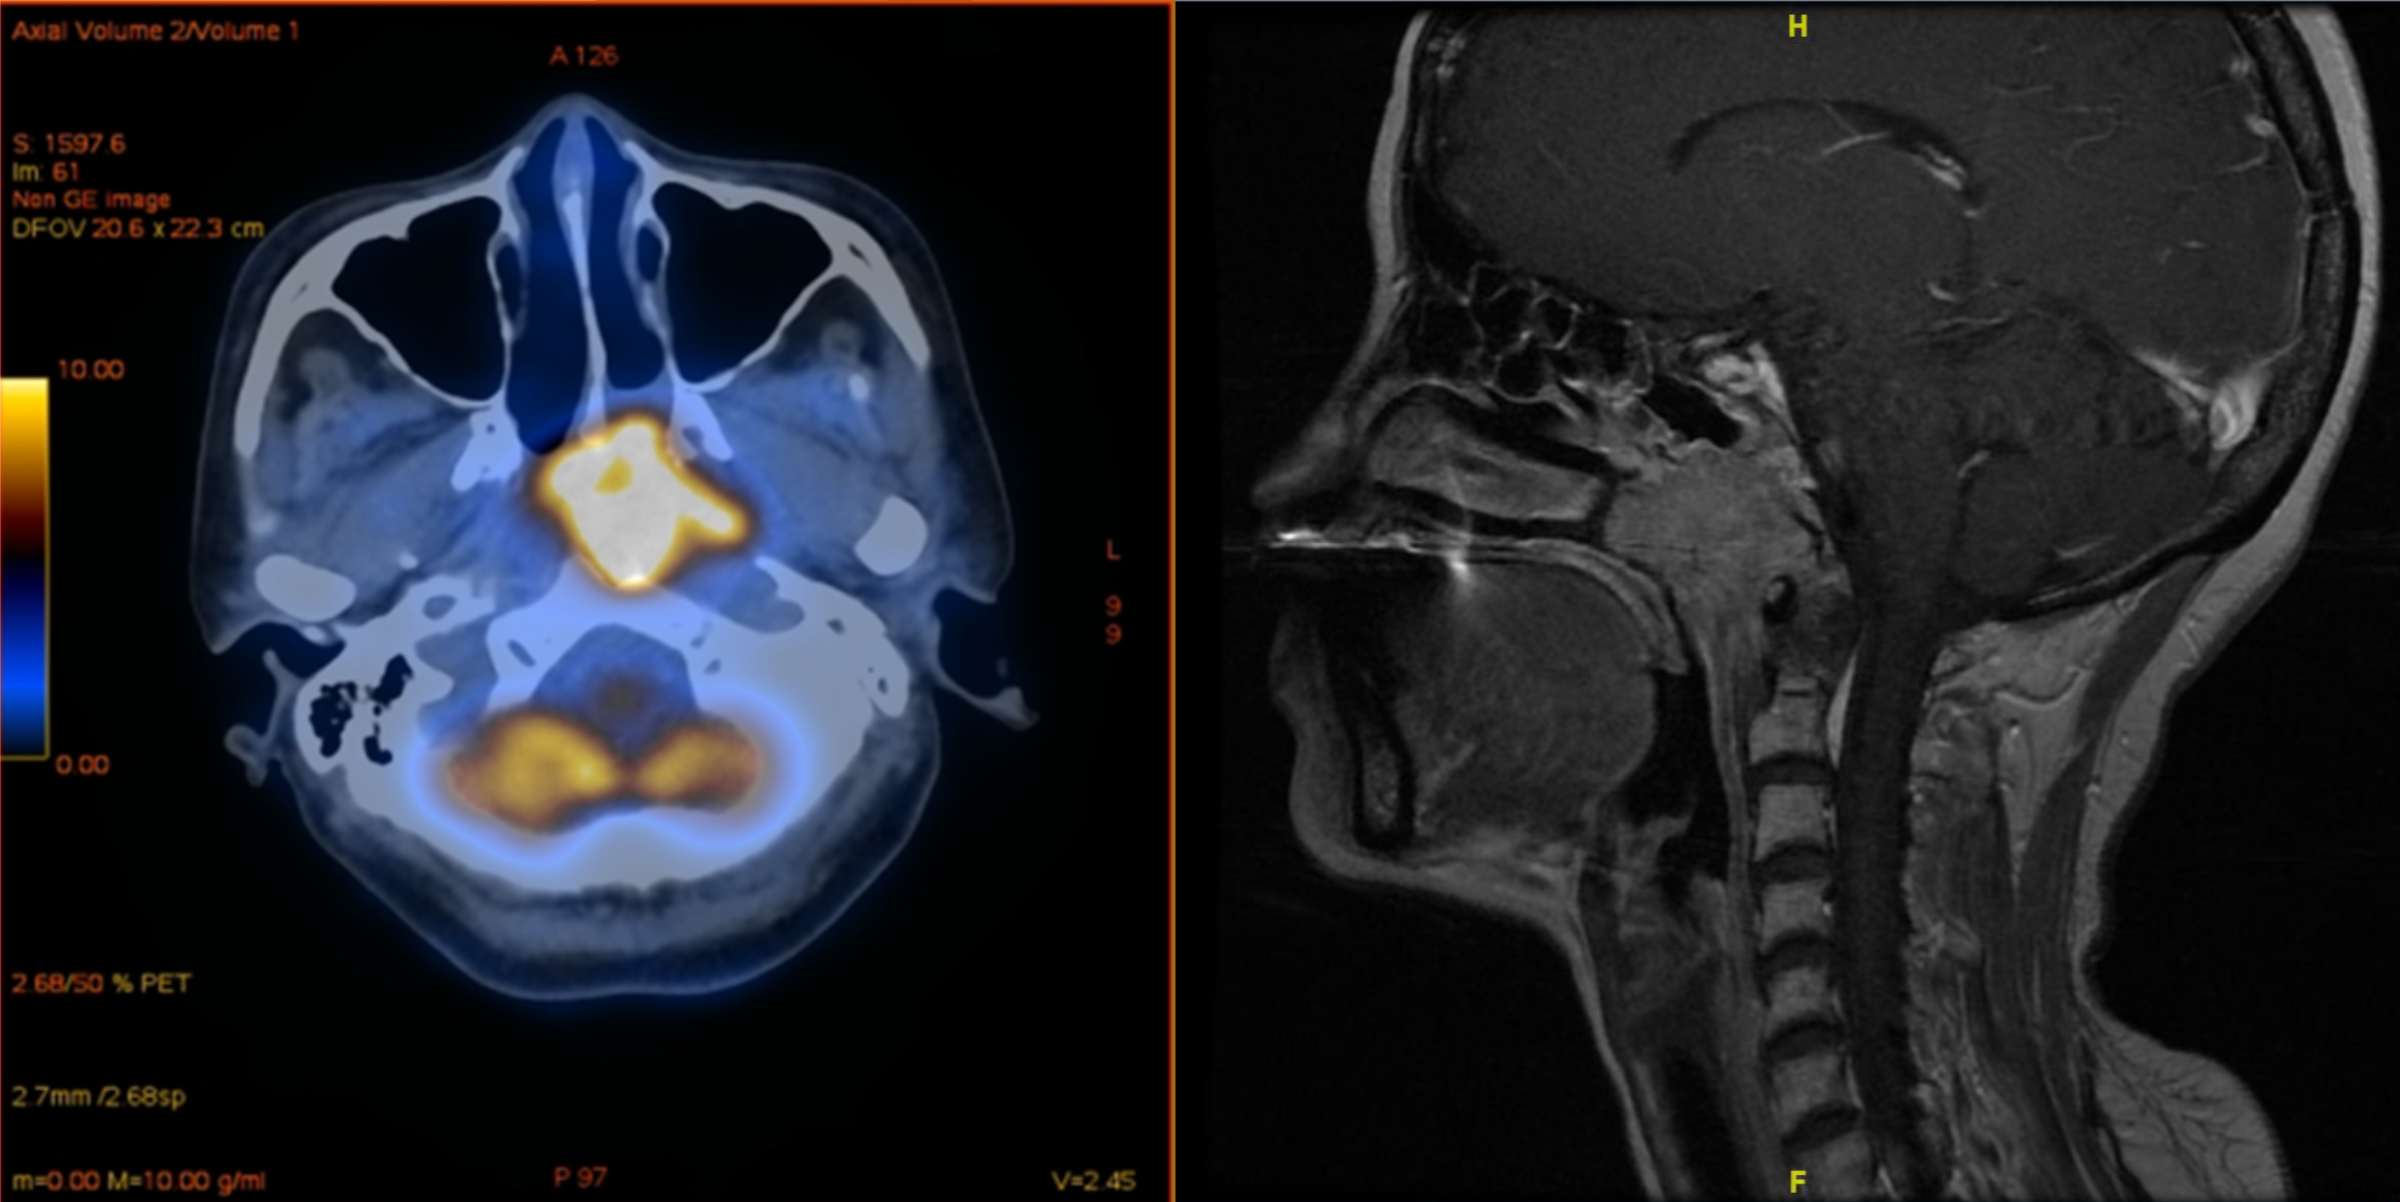

Menschen mit Nasenrachenkrebs werden häufig mit Medikamenten behandelt, die ihr Immunsystem gegen den Tumor aktivieren. Bislang befürchtete man, dass eine Impfung gegen Covid-19 den Erfolg der Krebstherapie mindern oder starke Nebenwirkungen hervorrufen kann. Eine aktuelle Studie der Universitäten Bonn und Shanxi in der Volksrepublik China gibt diesbezüglich nun Entwarnung. Demnach schlugen die Krebsmedikamente nach einer Vakzinierung mit dem chinesischen Impfstoff SinoVac sogar besser an als bei Ungeimpften. Die Ergebnisse erscheinen als „Letter to the editor“ in der Fachzeitschrift Annals of Oncology, sind aber bereits online abrufbar.

Nasenrachenkrebs ist hierzulande recht selten. In Südchina und anderen Ländern Südostasiens ist die Erkrankung dagegen weit verbreitet. Als Gründe vermutet man unter anderem den häufigen Einsatz von Klimaanlagen in den feuchten und heißen Regionen. Auch Ernährungsfaktoren scheinen eine wichtige Rolle zu spielen. In Taiwan gilt Nasenrachenkrebs inzwischen bei jungen Männern als eine der häufigsten Todesursachen.